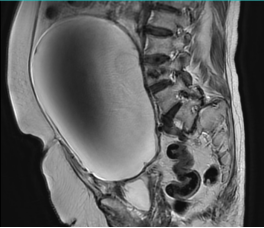

80岁曹奶奶(化名)30年前因子宫肌瘤接受了子宫切除术。半年前出现腹部胀痛,并逐渐加剧,到宁德市医院就诊后发现盆腹腔有一个巨大肿瘤,上界达剑突下。

这个肿瘤在曹奶奶的腹腔内占据了大量空间,甚至压迫到周围脏器,对于一个年过八旬、患有高血压、腰椎压缩性骨折术后等多种疾病的老年患者来说,手术风险呈几何级数增加。

妇科科主任、主任医师陈惠华介绍,单孔腹腔镜手术是一种非常精细的微创技术。手术只需要在肚脐附近开一个3厘米左右的小切口,不需要像传统腹腔镜那样先往肚子里充气。医生会先用特殊缝线在肿瘤表面缝一圈,像扎口袋一样,然后用细针穿刺到肿瘤内部,慢慢把里面的液体抽出来。抽液的同时要不断收紧缝线,还要在胸口压个沙袋帮助排液,等液体抽干净后就把缝线彻底扎紧,防止液体漏出来。最后在腹腔镜的引导下把肿瘤完整切除。

手术台上,如预期所料,曹奶奶的腹腔内因前次手术存在广泛粘连,肠管与肿物粘连,且输尿管紧贴肿物,这给手术分离带来了巨大挑战,主刀医生小心保护周围肠管、输尿管等重要结构,切除肿物,最终通过取物袋将肿瘤装袋完整取出。整台手术历时1个半小时。